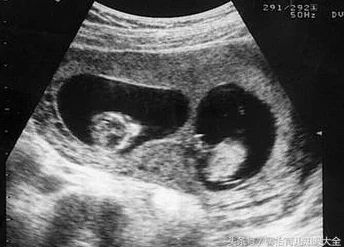

在现代社会中,家庭的构成越来越多样化。传统观念认为,血缘关系是家庭的重要基础,但随着科技的发展和社会观念的变化,人们开始重新审视这一点。当一个母亲发现自己怀的是儿子的孩子,而DNA检测却显示孩子的父亲另有其人时,这不仅仅是一个简单的事实,更是一场情感与道德的风暴。